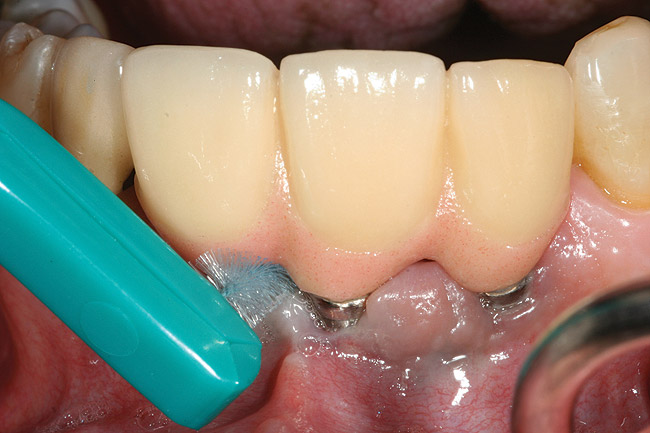

Locally delivered, controlled-release agents are a popular treatment adjunct and serve to augment scaling and root planing to help improve outcomes. Clinical studies have shown that use of such agents can provide an average of 0.5-mm additional pocket depth reduction over scaling and root planing alone, so the practitioner must weigh the cost-benefit ratio of using these products in each patient situation.39,40 A guideline for the appropriate use of locally delivered antimicrobials has been provided by the American Academy of Periodontology.41 These materials are contraindicated in patients with (1) multiple 5-mm pocket depths in one quadrant; (2) anatomic defects caused by periodontal diseases (intrabony defects); and (3) when the previous use of locally delivered agents has failed to control disease. As noted before, a follow-up reevaluation always should be completed to evaluate the success of any therapeutic intervention, generally at 4 to 6 weeks after treatment has been rendered30,31 (Figure 3A through Figure 3D).

Figure 4a  Use of a proxi-brush and large-diameter floss to perform plaque control around an implant-supported/retained prosthesis

Figure 4a

Figure 4b  Use of a proxi-brush and large-diameter floss to perform plaque control around an implant-supported/retained prosthesis

Figure 4b